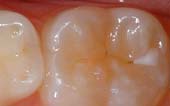

A sealant is a protective coating that is applied to the chewing surfaces (grooves) of the back teeth (premolars and molars), where four out of five cavities in children are found. This sealant acts as a barrier to food, plaque and acid, thus protecting the decay-prone areas of the teeth.